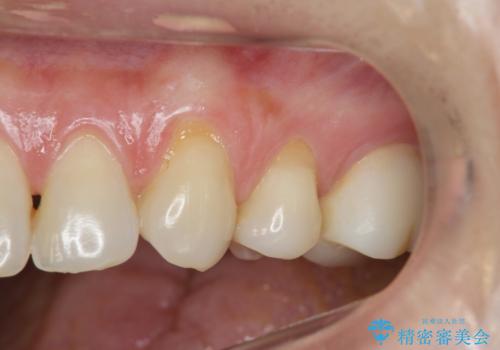

- 歯ブラシするたびに知覚過敏が辛く、改善を求めて来院されました。

過度なブラッシング圧により歯が削れてしまい、歯ぐきの下がりも認められます。

改善を図るため、結合組織移植を行い歯ぐきの再生を計画します。